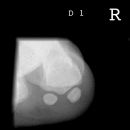

Sprinteraufn. Sesambein D1 tangential

Zentralstrahl

Auf Höhe des Caput metatarsale I im senkrechten Strahlengang tangential zur Plantarfläche.

Qualitätskriterien

Überlagerungsfreie Darstellung der Sesambeine und der Mittelfußköpfchen.